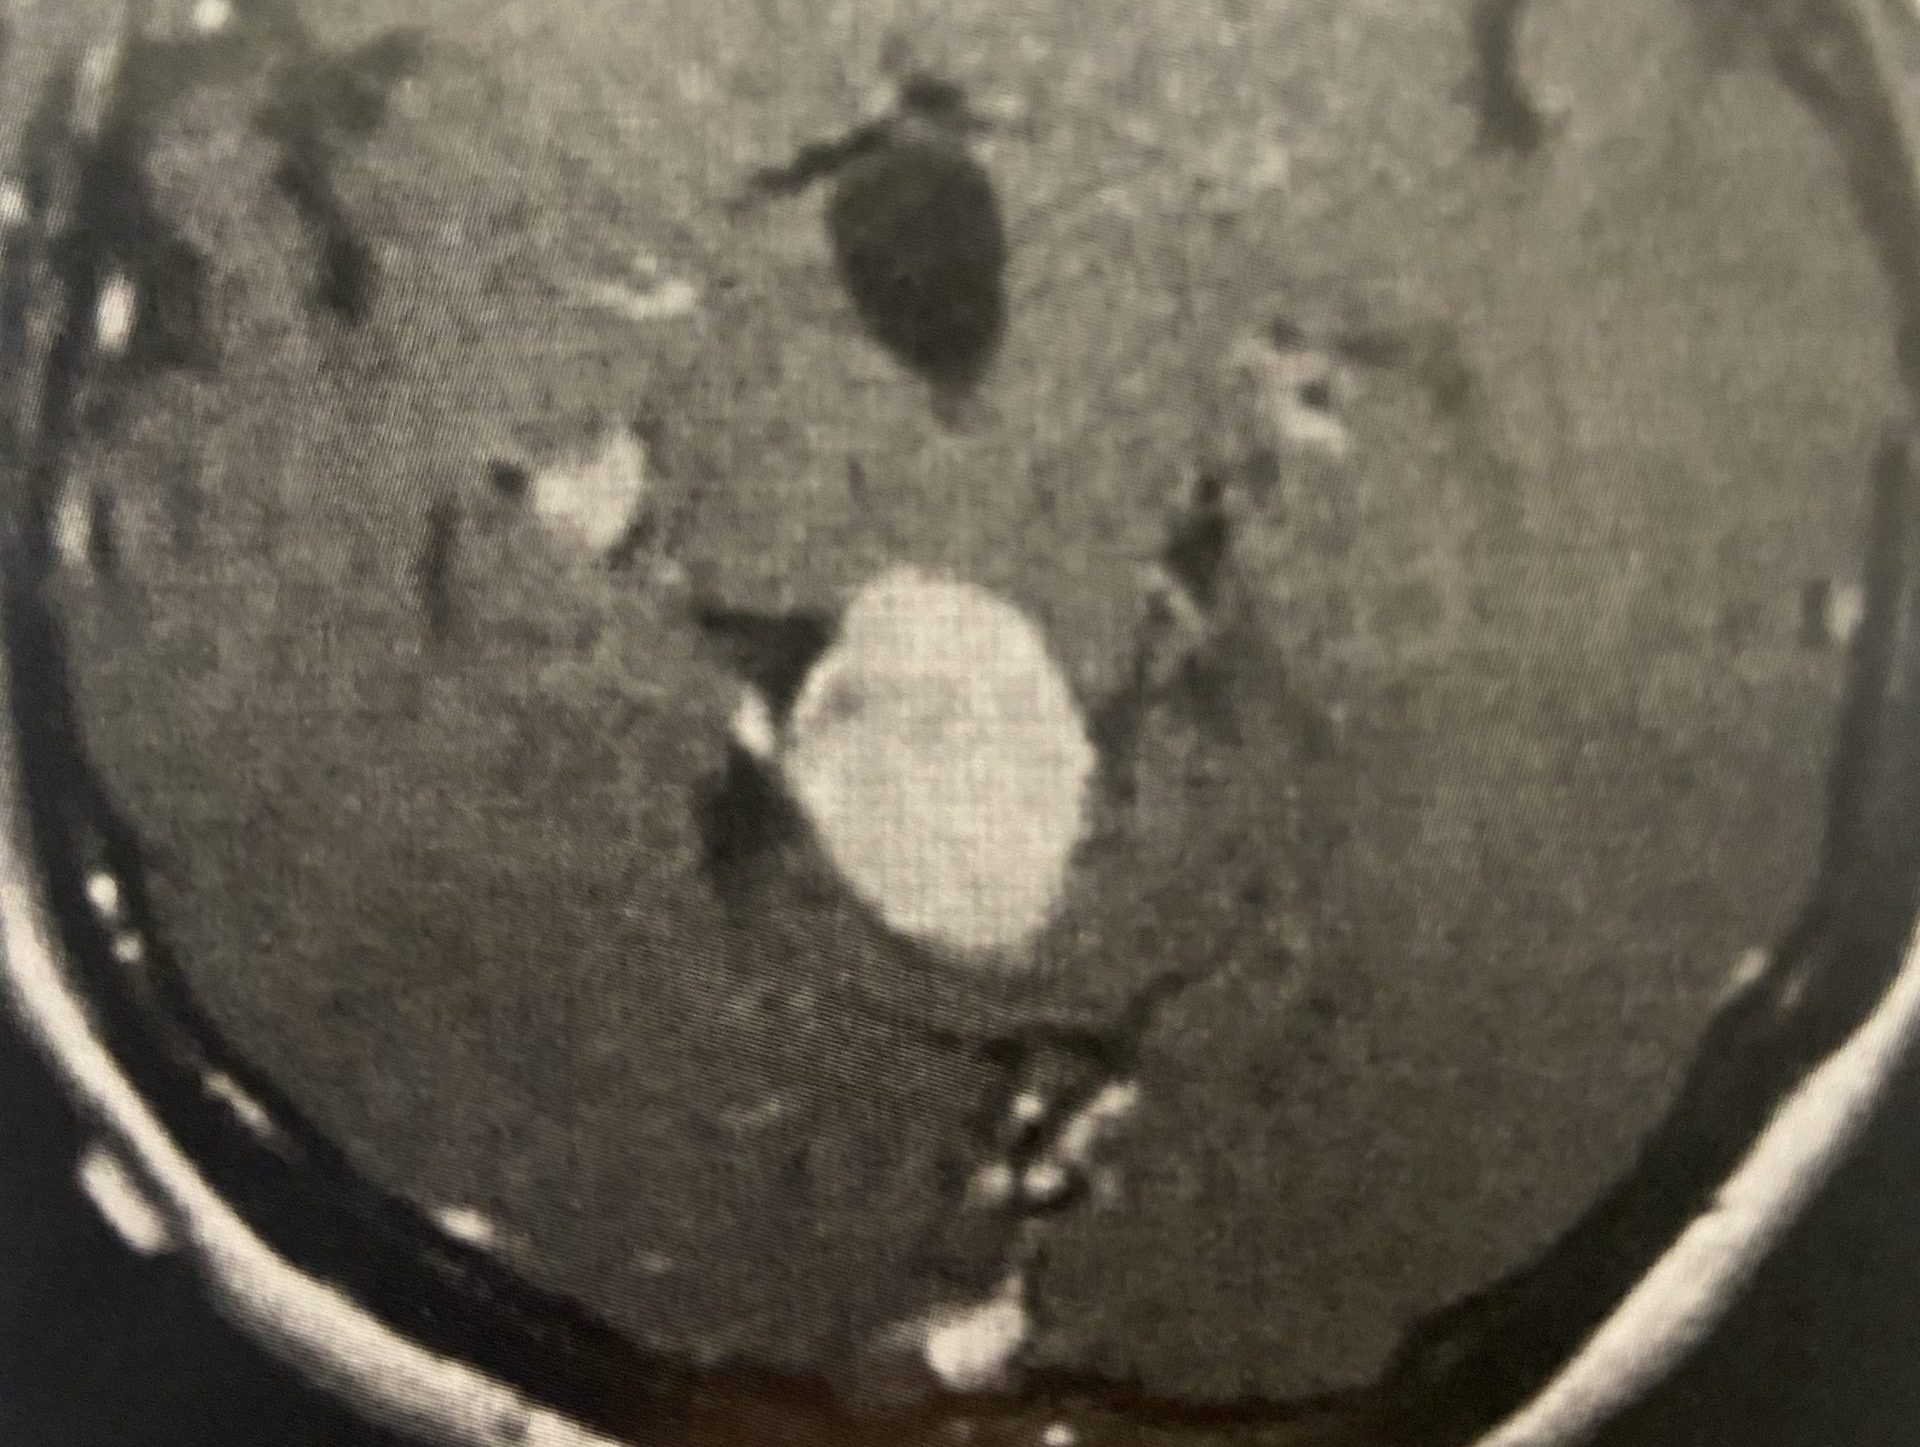

(Fig. 1) Sagittal T2 cervical MRI demonstrates significant C34 and C45 disc degeneration and osteophyte formation and instability status post anterior cervical discectomy and fusion C5-C7.